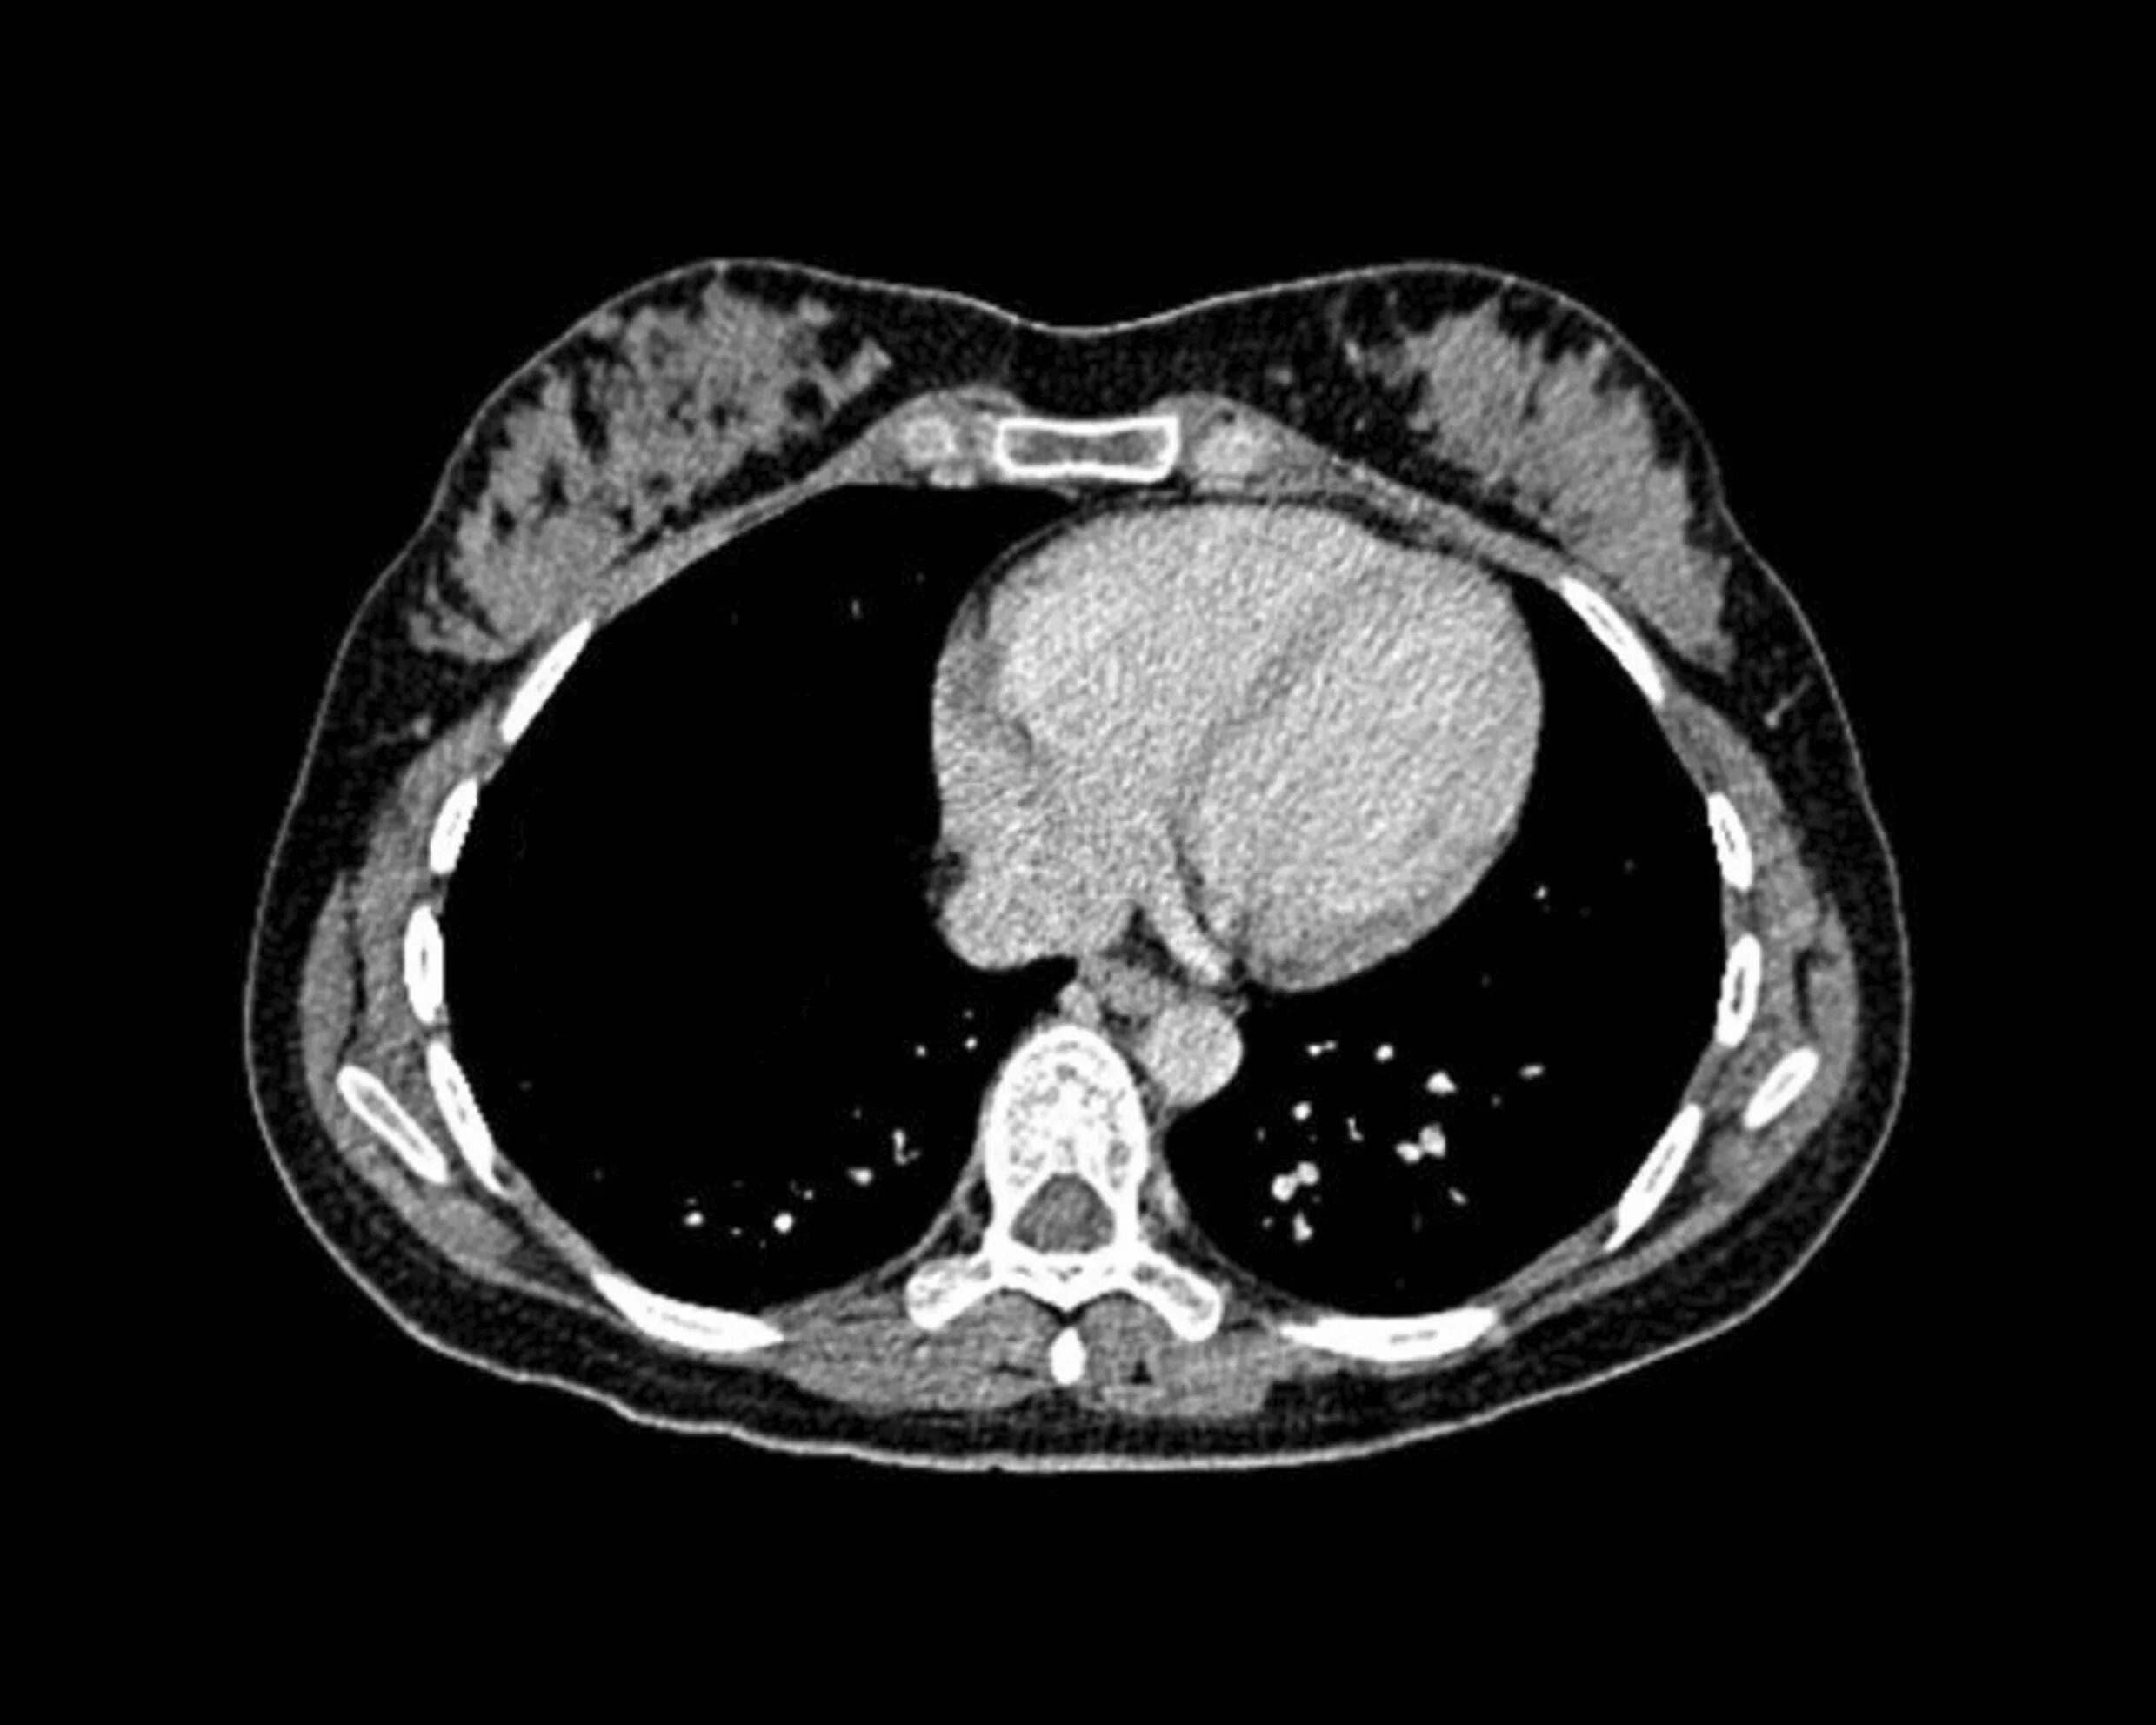

Скрининг кт